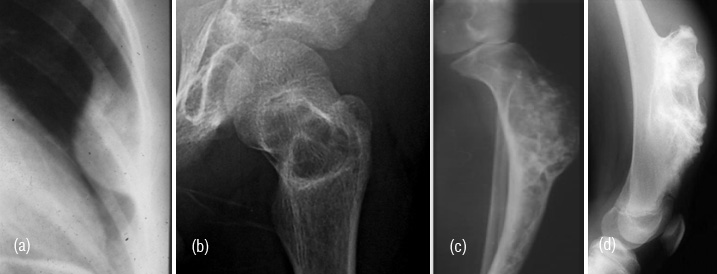

Post traumatic bone lesion

In avulsive lesions of apophysis, the healing phase of the lesion simulates a bone tumor such as pariosteal osteosarcoma (Figure 9ab). This is due to abundant callus and associated calcified hematoma with myositis ossificans. These lesions are well circumscribed without any soft tissue swelling. If one is not familiar with this entity, these may be mistaken for benign or malignant osteogenic tumors. Post traumatic myositis ossificans can occasionally simulate osteochondroma or other benign bone lesion (Figure 9cde). In a bedridden patient due to neurological cause’s dystrophic calcification/ ossification is commonly encountered in the soft tissues particularly in pelvic region which may be mistaken for an osseous tumor such as pariosteal osteosarcoma (Figure 9f).

Figure 9: (a) Avulsion injury at the attachment of rectus femoris to anterior inferior iliac spine, (b) Avulsion injury of the adductors to ischial apophysis. Note the abundant callus and myositis ossificans. (c) Post traumatic myositis ossificans, (d) Exostosis, (e) Myositis ossificans, (f) Pariosteal osteosarcoma.

Dystrophic calcification/ ossification

It occurs in patients with spinal cord injury or other neurological disorders. Excessive granulation tissue leads to fibroblastic proliferation leading to osteocytic activity (Figure 10a,b).

Figure 10: (a) Dystrophic ossification in bedridden patient, (b) Soft tissue ossifications in a patient with paraplegia.